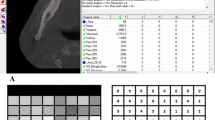

Preliminary investigation was performed to evaluate which values of textural features are connected to cortical bone, trabecular bone and soft tissue as a reference. A total of 29 samples of each of these regions of interests (ROIs) were analysed (Fig. 1).

The first step was to load an X-ray image to MaZda in .bmp file format (bit map). Then, the ROIs were marked with average 2444 pixels for the bone area and 2515 pixels for the material area. ROIs were marked on all images: green ROI was for material texture and the reference ROI (the red one) for bone (Fig. 2). The ROIs were normalised to share the same mean and standard deviation of grey level inside the ROI (μ ± 3σ, where μ and σ denote the mean and standard deviation of registered optical density, respectively).

Textural features calculated in this study. Radiograph samples taken from location presented in Fig. 2 (raw RTG). Below these radiograph samples, there are a series of maps of investigated texture features (SumOfSqrs, Entropy, DifEntr and LngREmph) which were analysed for 12 months of observation. The brighter areas in these maps indicate where a given texture feature is more intense

The components of texture analyses are the following (Fig. 3): sum of squares (SumOfSqrs), entropy (Entropy), difference entropy (DifEntr) for 5-pixel distance (all previous features derive from co-occurrence matrix) and long-run length emphasis moment (LngREmph) were utilised. All features were gathered in angles 0°, 45°, 90° and 135° from done pixel, and average value was later calculated. Features were calculated for the reference bone and for the substitute material: